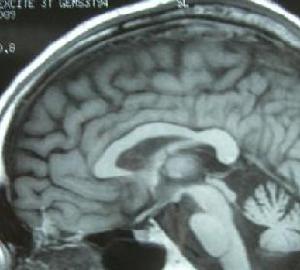

小腦萎縮小腦萎縮核磁共振成像(MRI)檢查:掃瞄腦部,可以見到病變進行中的小腦萎縮。